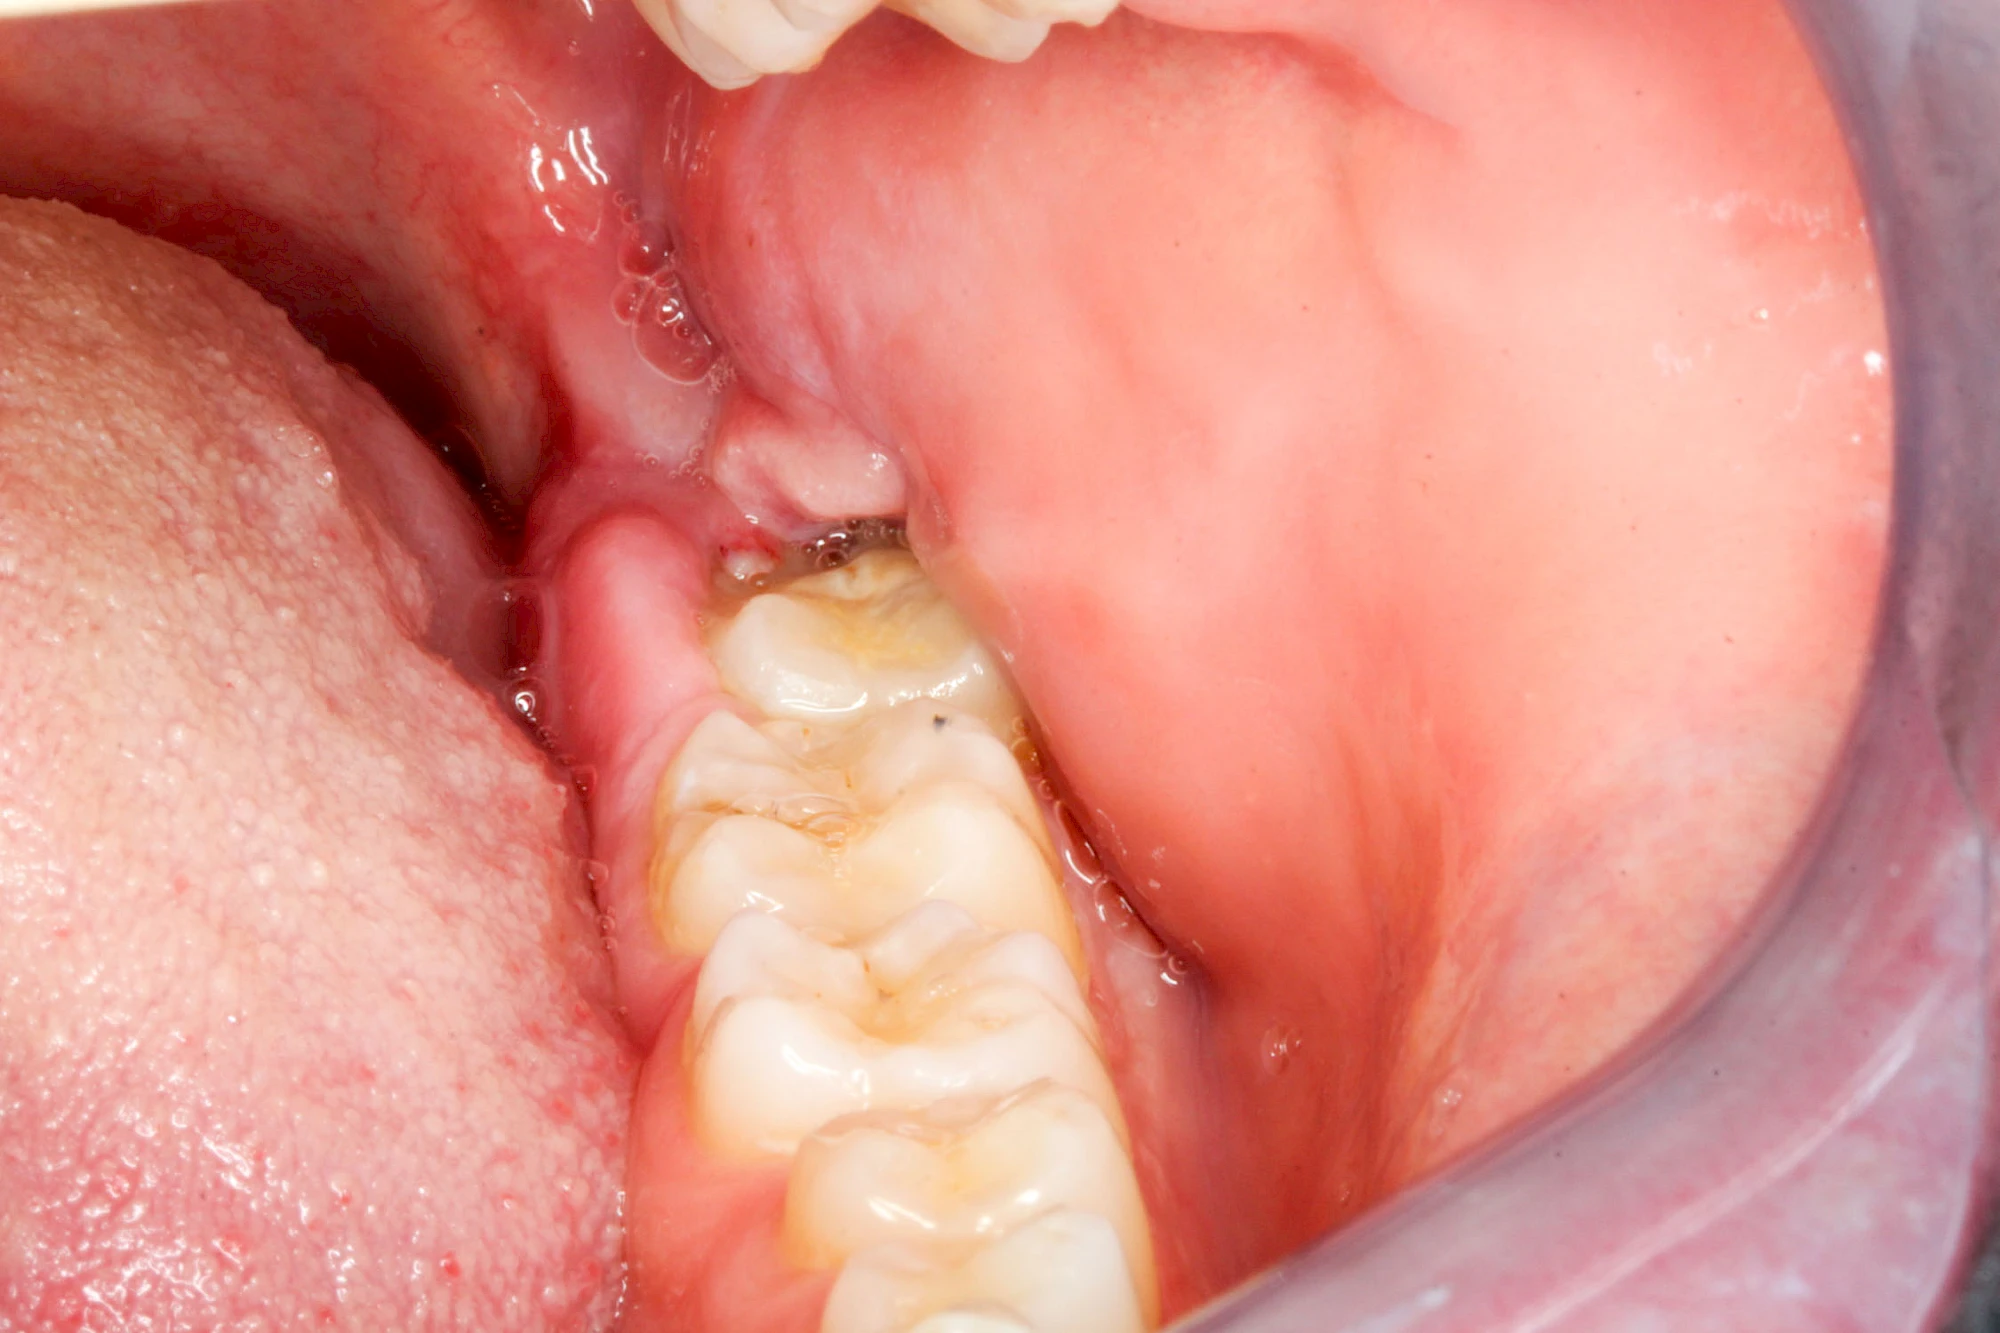

Im Laufe der menschlichen Entwicklung haben sich die Kiefer aufgrund unserer Nahrungsumstellung rückgebildet. Die Weisheitszähne haben daher oft keinen Platz mehr. Bei ca. 30 % der Menschen sind diese Zähne schon gar nicht mehr angelegt. Zum Teil liegen die Zähne versteckt (retiniert) im Kiefer und sind nicht sichtbar. Hin und wieder brechen die Zähne zwar durch die Schleimhaut, aber nicht vollständig – es handelt sich um einen erschwerten Zahndurchbruch (dentitio difficilis). Dann sind die Zähne noch teilweise bedeckt von einer "Schleimhautkapuze". Gehen hier Speisereste und Bakterien unter die Schleimhautkapuze kann sich eine sogenannte Schlupfwinkelinfektion bilden. Diese Entzündungen treten spontan auf, sind häufig sehr schmerzhaft und die Mundöffnung ist eingeschränkt. Hier ist umgehend der Zahnarzt zu kontaktieren.